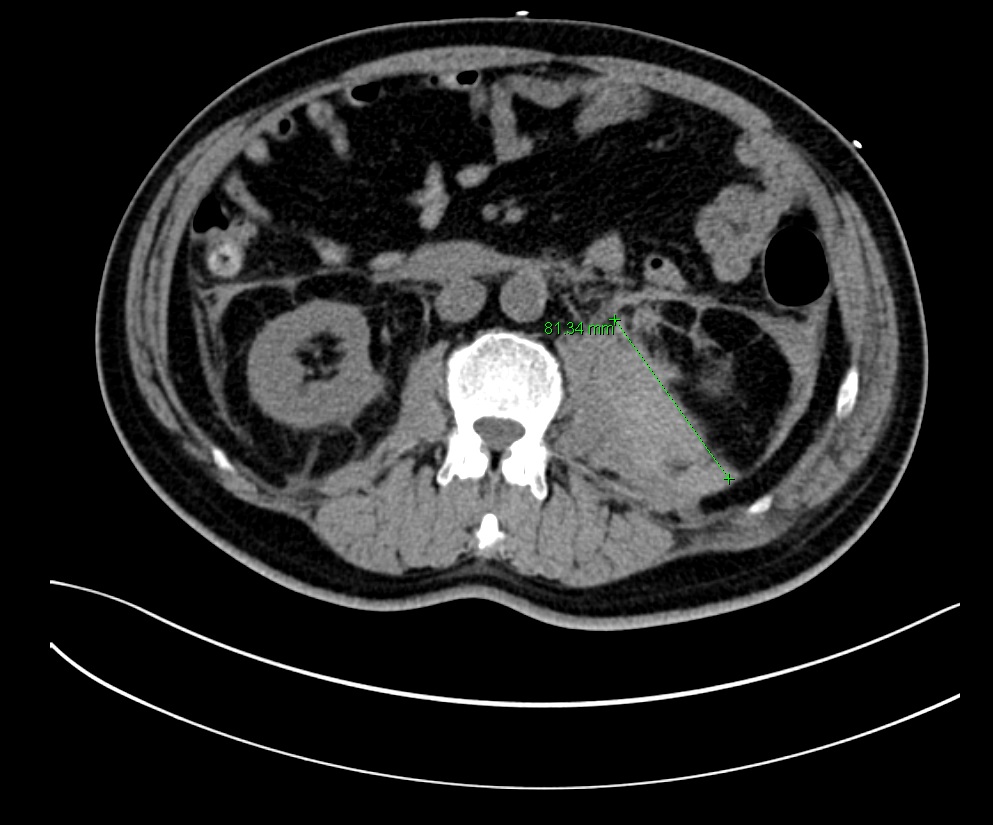

CT Aortogram showed no evidence of aortic dissection, but incidentally showed multiple pulmonary emboli and a large haematoma along the left psoas muscle, extending into the pelvis (7.5 x 8.0 x 16.1 cm). There were also filling defect noted in the inferior vena cava, left external iliac/femoral vein, suspicious of thrombosis.